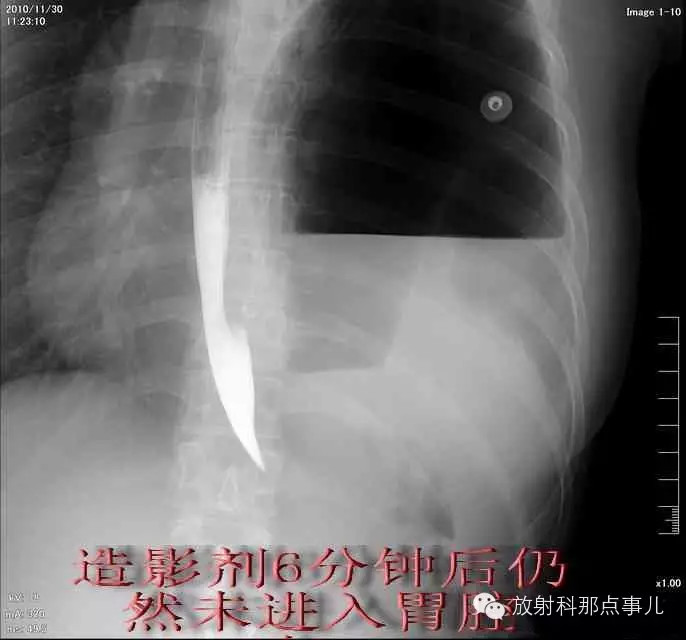

门诊腹部透视发现左侧胸腔巨大气液平面,为排除膈疝口服钡剂,但造影剂未见进入胃内。嘱住院,外科给予胃肠减压、补液等处理常规处理(未引流出明显气、液体)。5个半小时后再次检查,见少量造影剂进入消化道;为进一步了解情况,予泛影葡胺分别经胃管推注及口服,但均未进入胃内。当天进行外科急诊手术。

更正:检查时间在左上方。